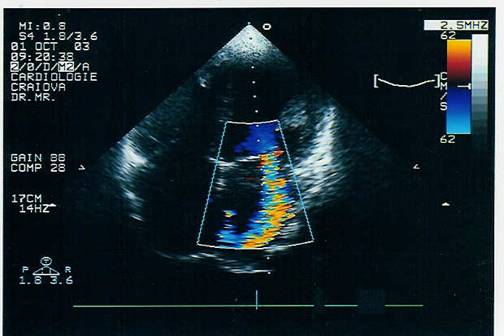

ECO color si Doppler pulsat

permite cuantificarea regurgitarii evidentiind velocitatea

maxima in sistola in atriul stang si se poate aprecia lungimea

si aria jetului regurgitat pentru aprecierea gradului regurgitarii.